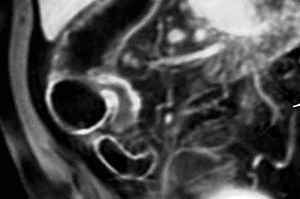

Para los pacientes con EC el riesgo de padecer una fístula durante su vida se sitúa entre el 20 y el 40%. En el caso de las fístulas perianales el riesgo es acumulativo y aumenta con el paso de los años: del 21% a los 10 años, al 26% después de los 20 años de enfermedad18. En el diagnóstico por imagen de las fístulas anorrectales la fistulografía está siendo reemplazada por la RM, que ha demostrado gran precisión a la hora de determinar y diferenciar los trayectos fistulosos y abscesos8,19,20. Las ventajas de la RM frente a la TC son la mayor resolución tisular en el estudio de partes blandas de la región pélvica y la mayor resolución espacial.

La RM es una técnica que surge con un gran potencial en el estudio del intestino delgado, fundamentalmente en pacientes de este tipo, puesto que no supone radiación ionizante. Se trata de una patología inflamatoria crónica, de carácter recurrente, en pacientes jóvenes con una gran esperanza de vida, en los que hay que minimizar la exposición a radiaciones ionizantes, y probablemente en un futuro no lejano la RM va a ejercer un importante papel en el estudio de estos pacientes. En concreto la RM ha demostrado gran precisión en el estudio de las fístulas anorrectales, a la hora de determinar y diferenciar los trayectos fistulosos7,8.